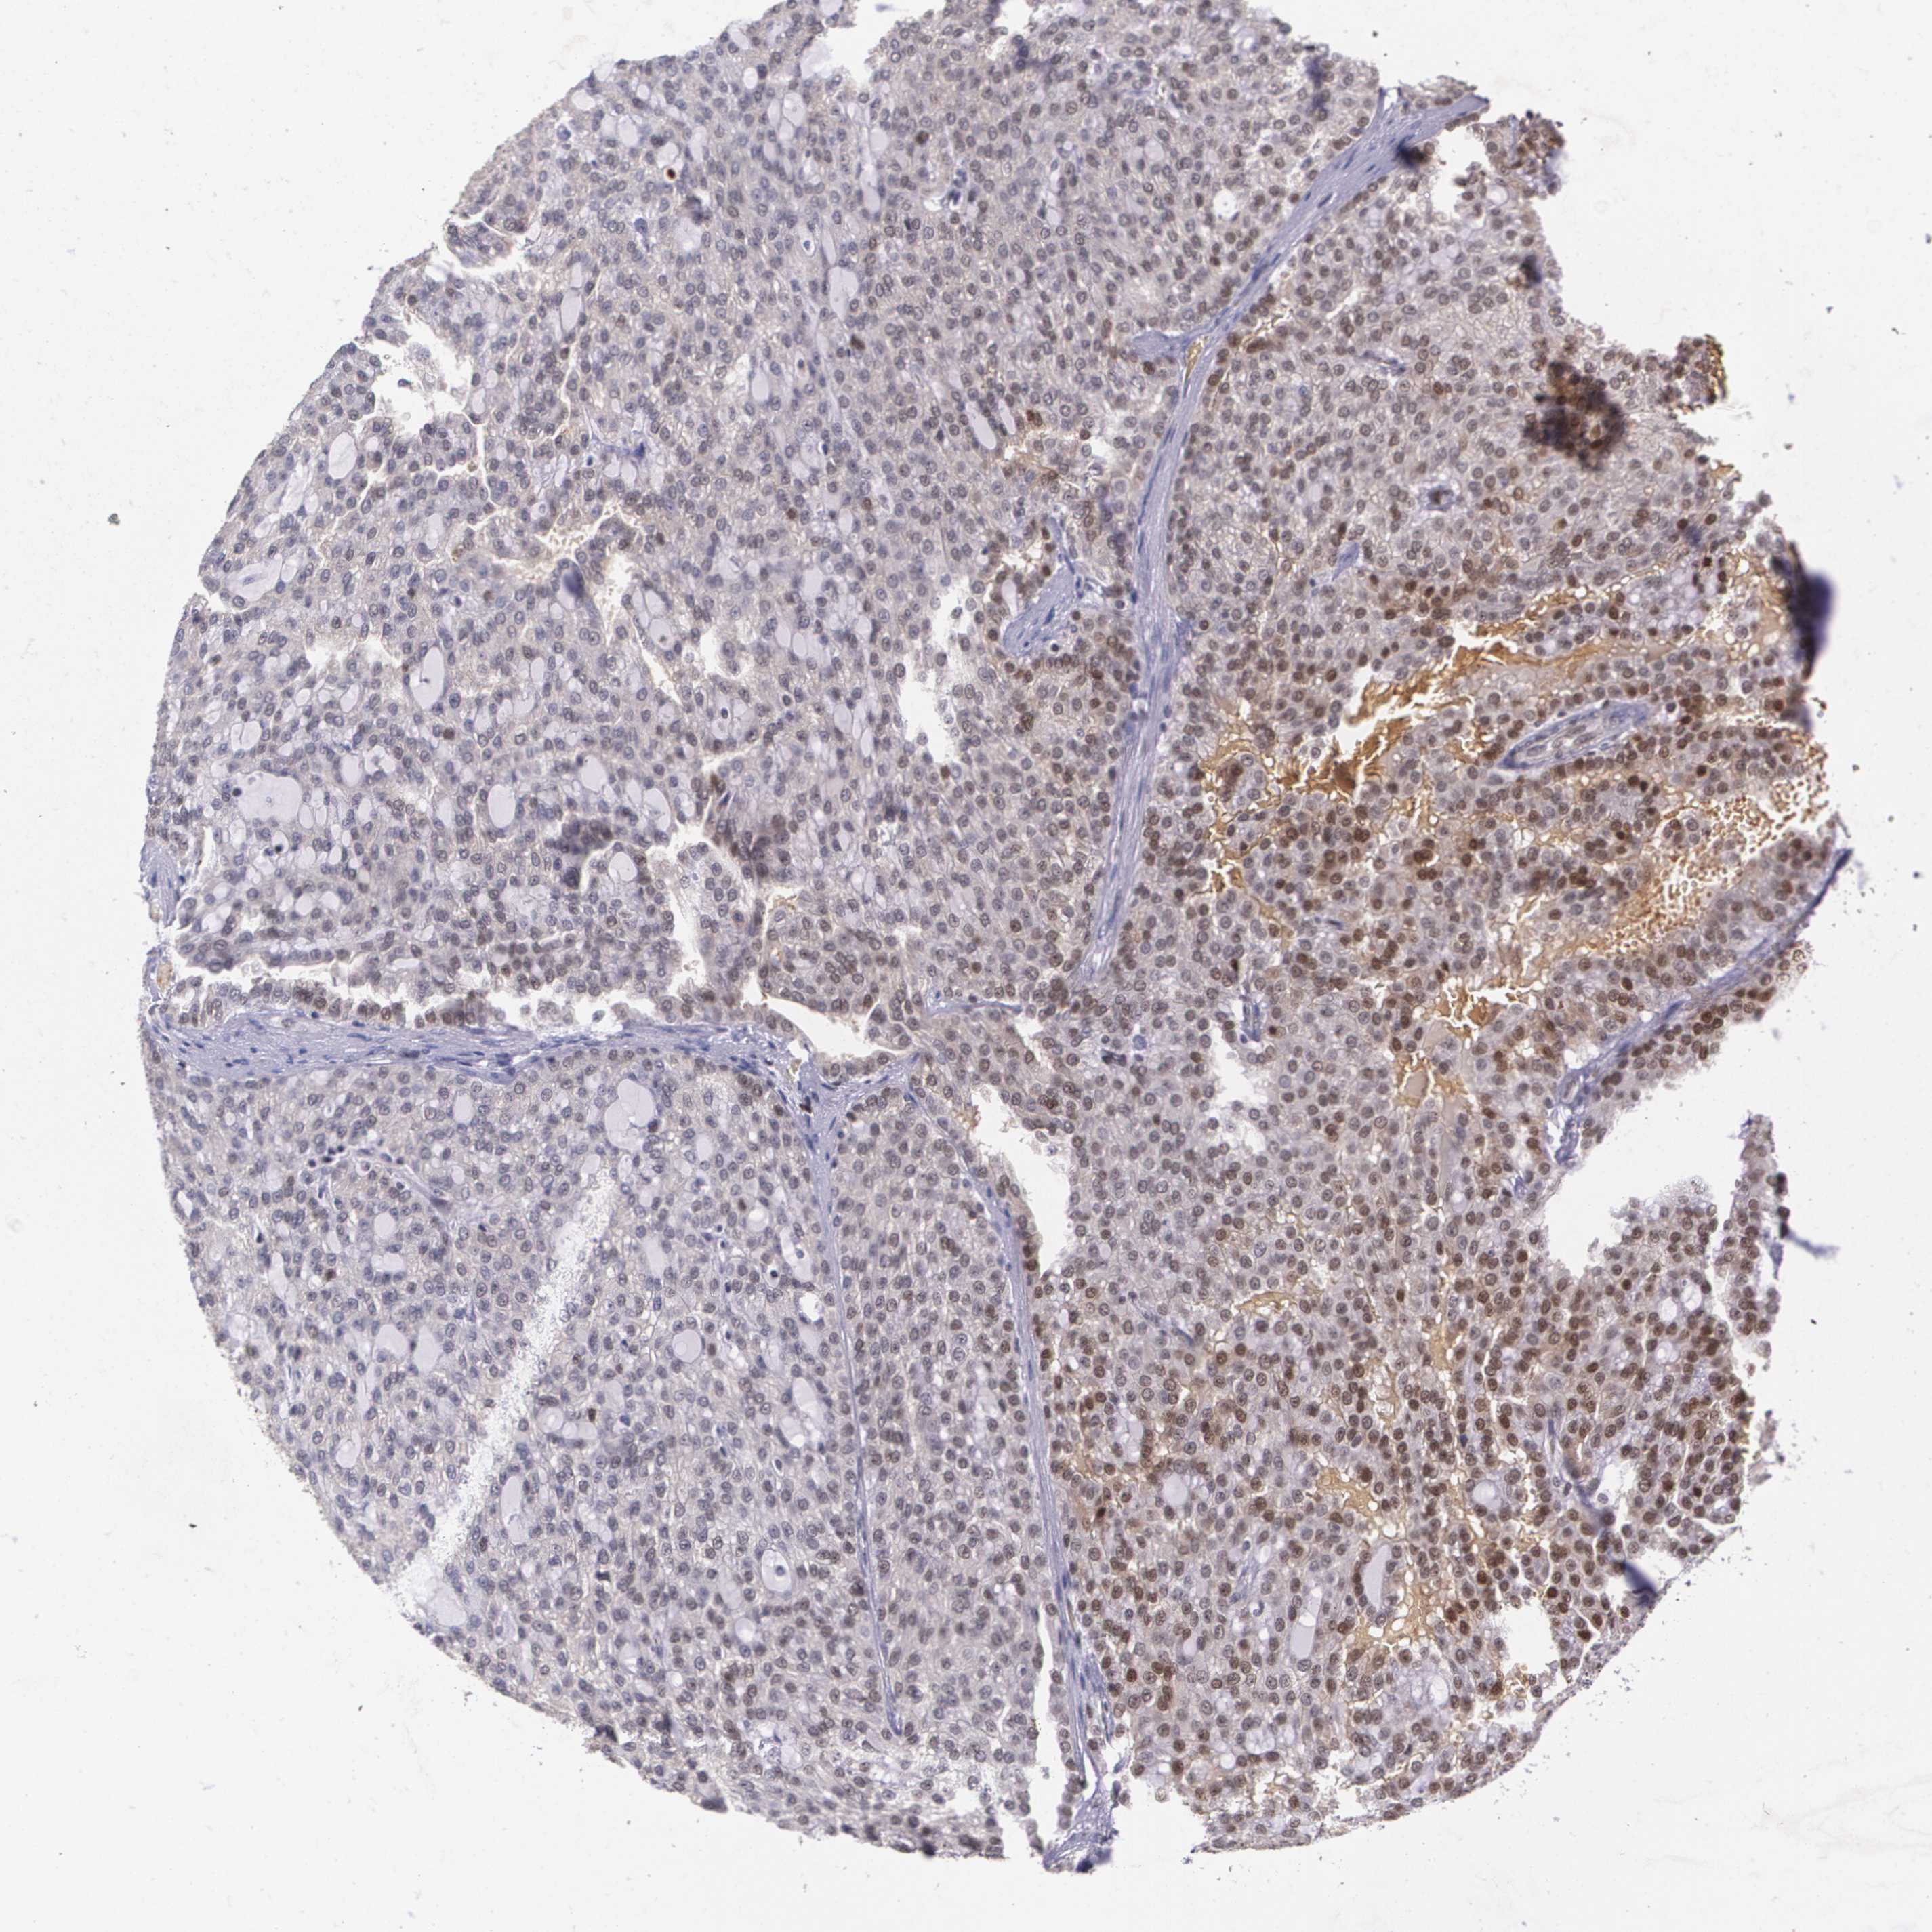

KIDNEY RENAL CLEAR CELL CARCINOMA (TCGA) - Interactive survival scatter ploti

The Survival Scatter plot shows the clinical status (i.e. dead or alive) for all individuals in the patient cohort, based on the same data that underlies the corresponding Kaplan-Meier plots. Patients that are alive at last time for follow-up are shown in blue and patients who have died during the study are shown in red.

The x-axis shows the expression levels (FPKM) of the investigated gene in the tumor tissue at the time of diagnosis. The y-axis shows the follow-up time after diagnosis (years). Both axes are complimented with kernel density curves demonstrating the data density over the axes. The top density plot shows the expression levels (FPKM) distribution among dead (red) and alive patients (blue). The right density plot shows the data density of the survived years of dead patients with high and low expression levels respectively, stratified using the cutoff indicated by the vertical dashed line through the Survival Scatter plot. This cutoff is automatically defined based on the FPKM cutoff that minimizes the p-score. The cutoff can be changed by dragging the vertical line or by entering a cutoff value in the square labeled "Current cut-off".

Under the Survival Scatter plot the p-score landscape (black curve; left axis) is shown together with dead median separation (red curve; right axis). Dead median separation is the difference in median mRNA expression between patients who have died with high and low expression, respectively. It is calculated as follows: median FPKM expression of dead patients with high expression - median FPKM expression of dead patients with low expression. This is intended to aid the user in visually exploring custom cutoffs and the associated p-scores and dead median separation.

Individual patient data is displayed and can be filtered by clicking on one or more of the category buttons on the top of the page. Categories describing expression level and patient information include: high, low, alive, dead, female, male and tumor stages. The scale of the x-axis can be toggled between linear and log-scale by clicking on the "x log" button. Mouse-over function shows TCGA ID, patient information and mRNA expression (FPKM) for each patient.

& Survival analysisi

Kaplan-Meier plots summarize results from analysis of correlation between mRNA expression level and patient survival. Patients were divided based on level of expression into one of the two groups "low" (under cut off) or "high" (over cut off). X-axis shows time for survival (years) and y-axis shows the probability of survival, where 1.0 corresponds to 100 percent.

MGMT is potential prognostic, high expression is favorable in Kidney Renal Clear Cell Carcinoma (TCGA)

Best expression cut offi

Based on the FPKM value of each gene, patients were classified into two groups and association between prognosis (survival) and gene expression (FPKM) was examined. The best expression cut-off refers the FPKM value that yields maximal difference with regard to survival between the two groups at the lowest log-rank P-value. Best expression cut-off was selected based on survival analysis .

When clicking on this number, the vertical dashed line indicating cut-off, the interactive survival plot, and the Kaplan-Meier curve will be adjusted to show results based on the best expression cut-off.

: 23.73

TCGA RNA samplesi

RNA-seq data is reported as average FPKM (number Fragments Per Kilobase of exon per Million reads), generated by the The Cancer Genome Atlas (TCGA) .

Normal distribution across the dataset is visualized with box plots, shown as median and 25th and 75th percentiles. Points are displayed as outliers if they are above or below 1.5 times the interquartile range. FPKM values of the individual samples are presented next to the box plot.

Average pTPM 35.3

Number of samples 521